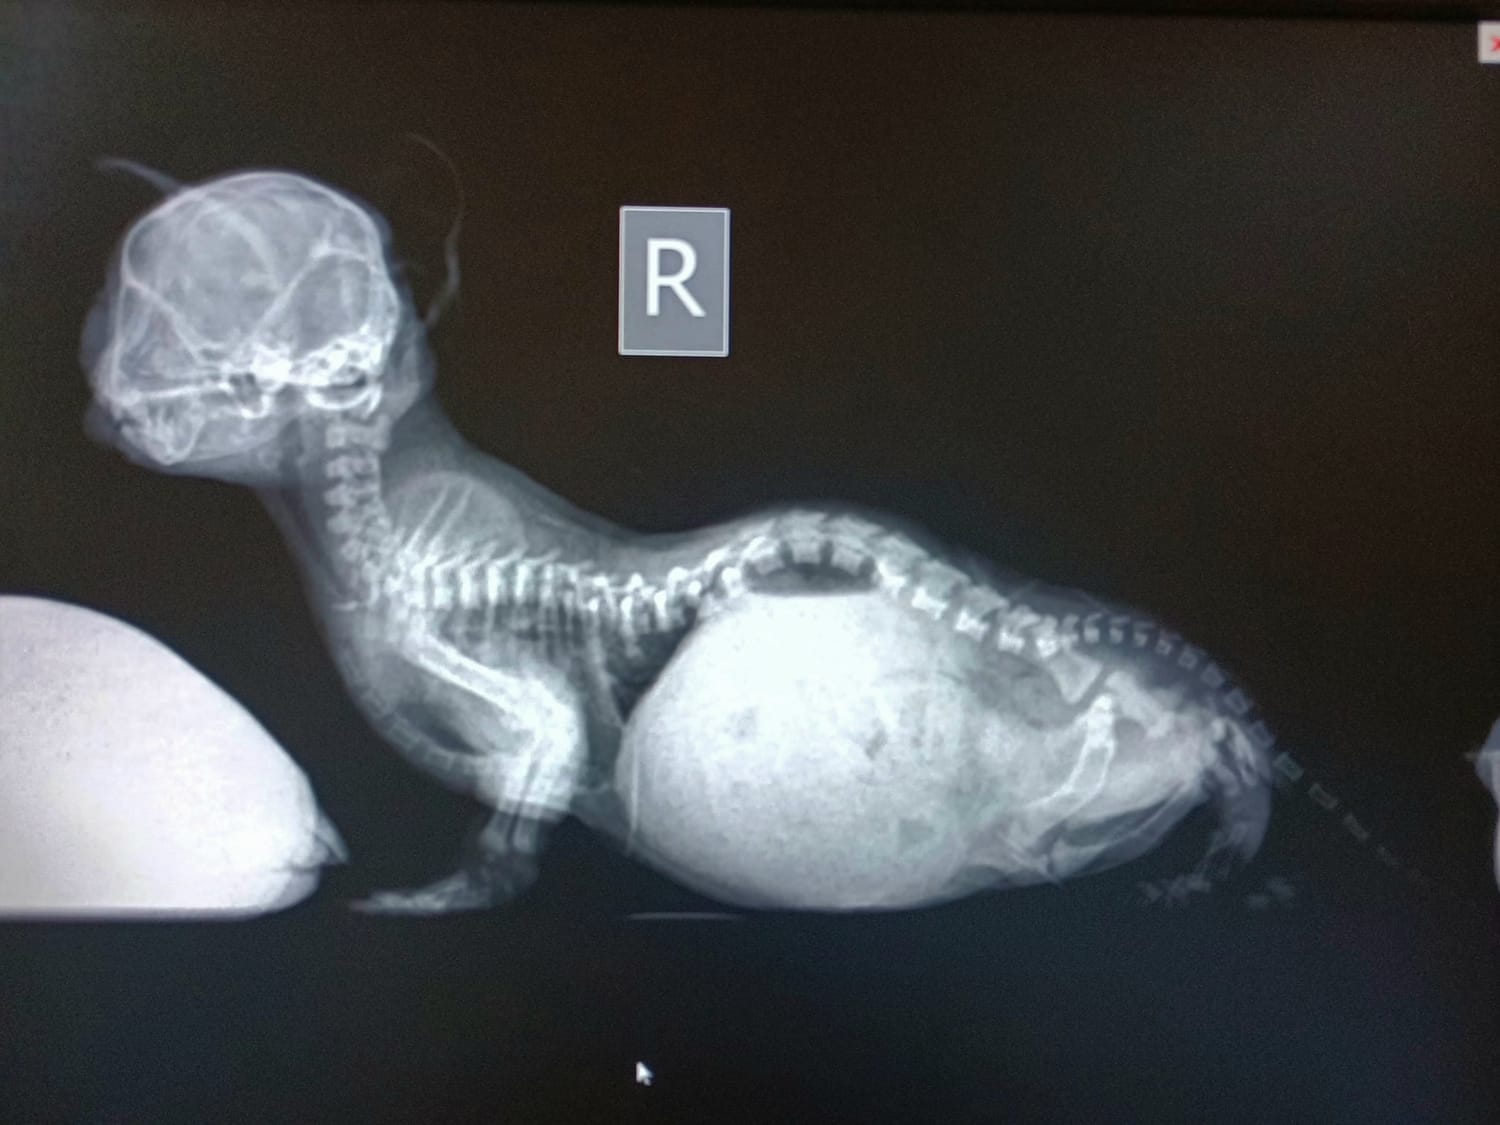

This is where I was contacted by a vet friend who performed Primrose's surgery. She had taken the kittens home as had an incubator and oxygen; the kittens were not in good shape and needed all the help they could get. After liaising with the vets, the RSCPA and local rescue, we formulated a plan for the kittens and I took them home to try and save. Upon collecting the kittens, I could see they were smaller than full-term new-born kittens, had diarrhoea and were hypothermic. The most deformed kitten had a strange body shape, appearing bloated with deformities and shortness of all 4 legs. This was the kitten I had the least hope for, it looked as if her legs had been put on back to front and it did not appear as though she could bend or place her legs and paws in a normal fashion.

Sadly, before long it was clear these kitten's prognosis was just as grim as we had anticipated. They required oxygen supplementation, nebuliser treatments, tube feeding, glucose, injectable fluids and higher incubator temperatures. More worryingly, these kittens were not able to digest any strength of formula without experiencing diarrhoea. The kittens were also exhibiting signs of infection so we started antibiotics. Over the next 48 hours, two of the three remaining kittens passed away despite every effort to save them. Their remaining sibling however (the most deformed kitten) was holding on. I had actually sent a message the day before to say I thought this kitten was not going to survive the night! It seemed a miracle that she had somehow managed to survive longer than her littermates, and at just 59 grams in weight. Healthy new-born kittens typically weigh between 85-110 grams. To put her size into context, this kitten was so tiny that she was about the same size as a cotton bud. This made it difficult to determine what gender she was, we even called her Evan in the first few days because we thought she may be a boy (sorry Suzi!).

As well as managing her digestive difficulties, we also had to implement an intensive regime to try and resolve her skeletal deformities. Thankfully, kitten bones, ligaments and tendons are soft, meaning these types of deformities can be improved with early intervention (before the bones solidify.) This involved daily splinting of her chest and legs to try and correct their shape as well as physiotherapy every 2 hours ... yep, every 2 hours day and night Suzi was fed, toileted and had a physiotherapy session.

This was pretty tough for Suzi since she had all four legs and her chest in tape and splints which could not have been much fun. Having said that, if this was not done for Suzi, she would have never been able to walk and her chest deformity would have compressed her heart and lungs, making it harder for her to breathe and ultimately, given her a much poorer prognosis.

Sadly, cases like Suzi don't always have such a fantastic outcome. Most of the time, premature puppies and kittens are not given the specialist care they require and usually pass away. Those with limb deformities are often left without treatment for weeks if not months. Heartbreakingly by this point, corrective physiotherapy and splinting regime is more gruelling, emotionally taxing on the puppy or kitten and less likely to be a success; with surgery often being a last resort. Suzi did not require any surgery and was able to start walking by 5 weeks of age.